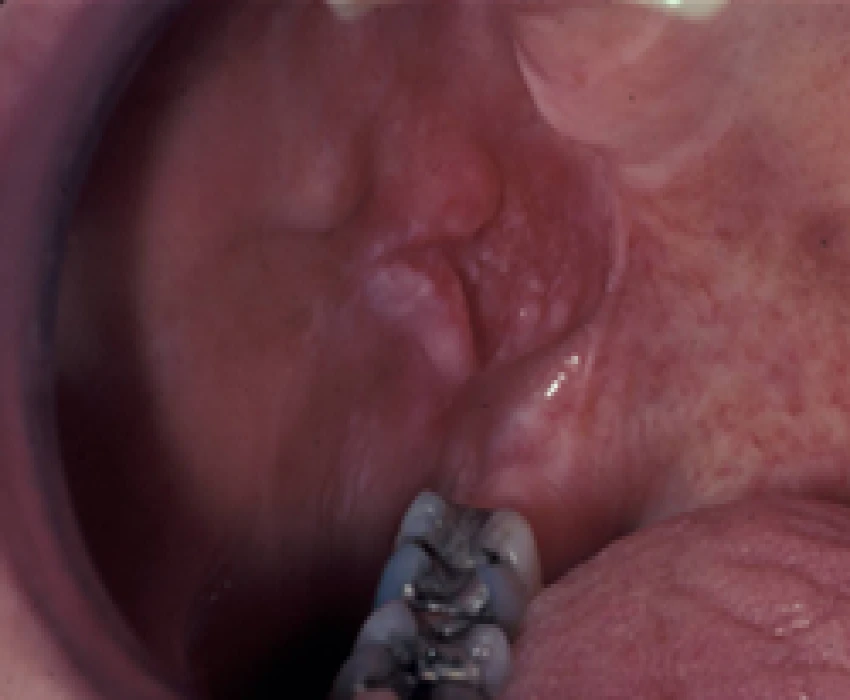

The red and white lesions include different type of lesions and to understand the various colors of these lesion one has to know, the color of oral mucous which depends on the degree of keratinization, dilation, and concentration of blood vessels, the amount of melanin pigment present in the epithelium and thickness of the epithelium. The professional require a skillful knowledge to diagnose and distinguish between these lesions and clinical correlation plays a very important role in diagnosing apart from histological reports. Dr Ankur has a deep insight in the above area.